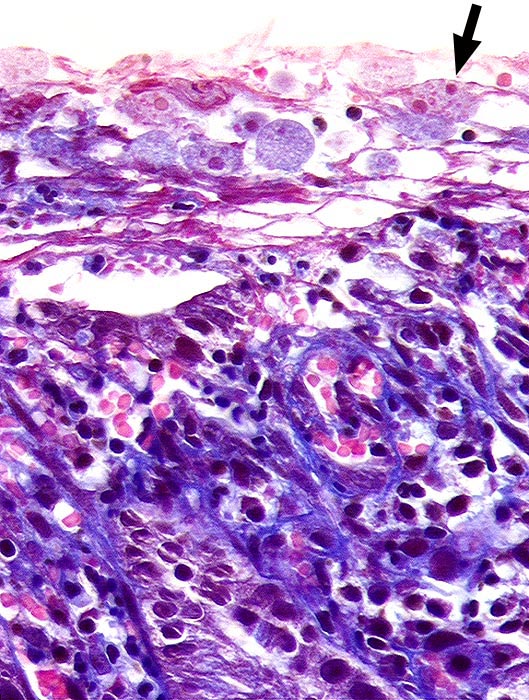

PathoPic ID 497 - Amöben

Amöben

Entzündung infektiös

Kolon

Darm, Anus

Auf dem Oberflächenepithel liegen zahlreiche Amöben mit feinkörnigem hellblauem Zytoplasma. Ein Teil davon mit

►

phagozytierten Erythrozyten.

Histologie